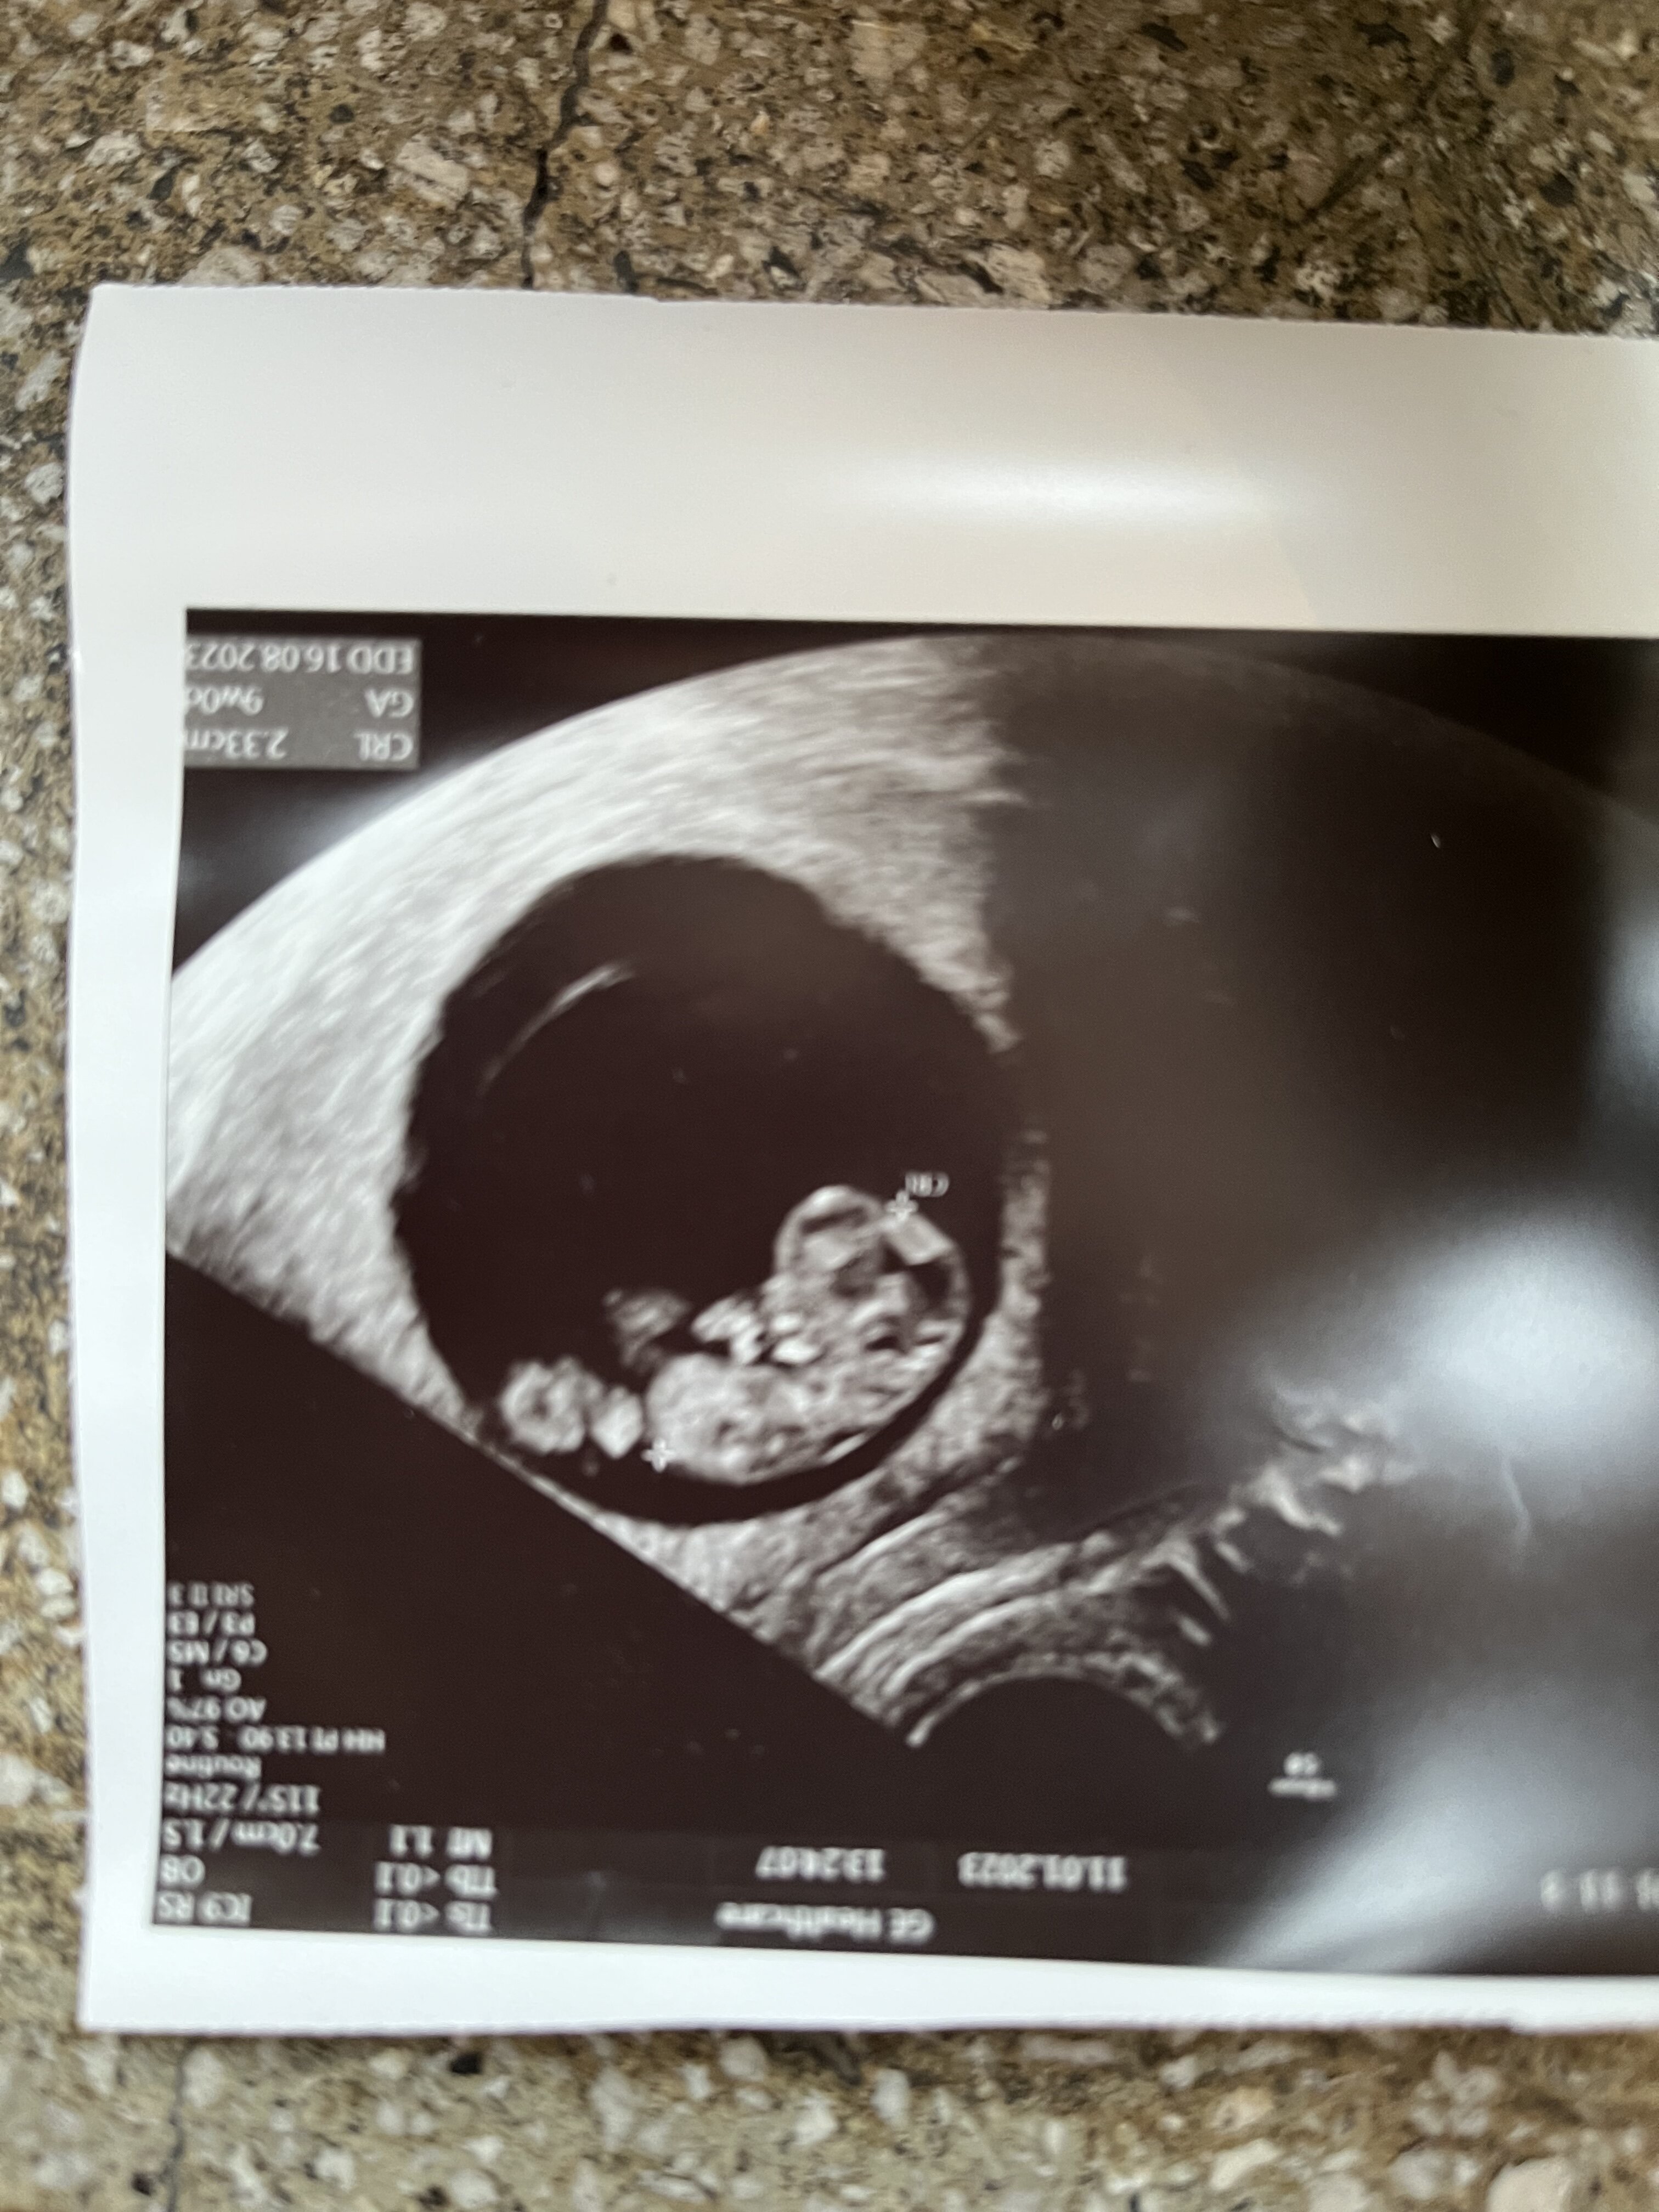

Wszystko okej! Wyszedł dzisiaj 9 tydzień równo (nie 9+1 jak przewidywaliśmy), ale się nie martwimy

Wszystko okej! Wyszedł dzisiaj 9 tydzień równo (nie 9+1 jak przewidywaliśmy), ale się nie martwimyserce ładnie bije, żadnych krwiaków, ani innych